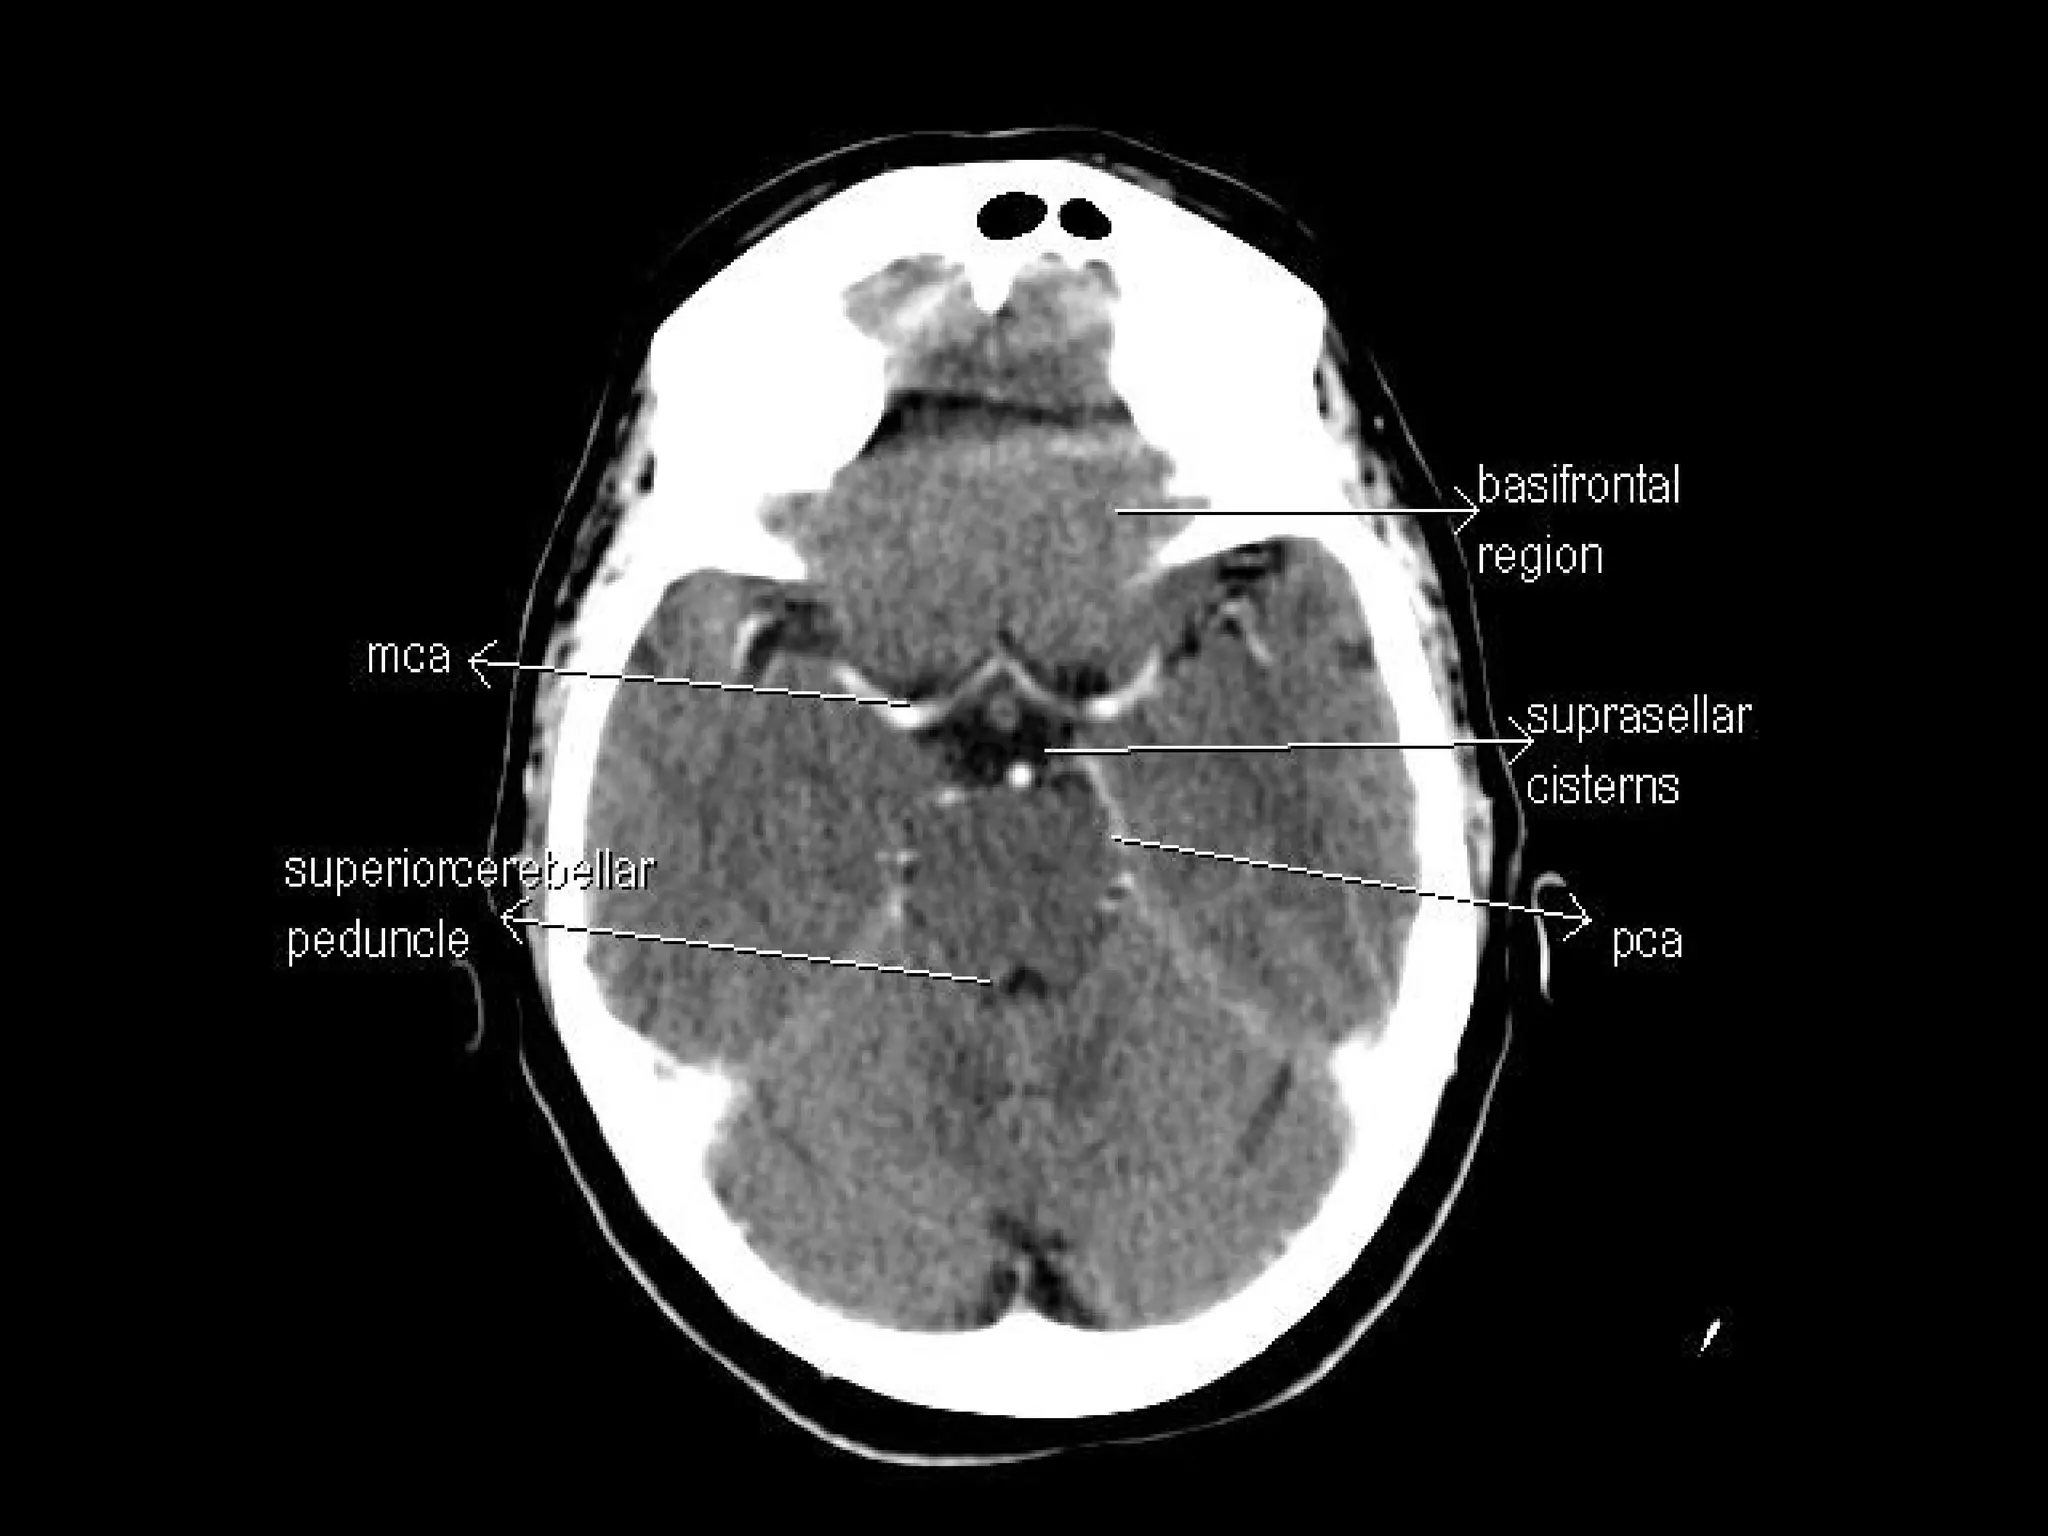

Radiographers are medical professionals who perform diagnostic imaging examinations and procedures to help physicians diagnose and treat diseases. They work under the supervision of radiologists to operate X-ray, CT, MRI, ultrasound and other medical imaging equipment and must have a strong understanding of human anatomy and pathology. Radiographers are responsible for correctly positioning patients, ensuring proper imaging techniques are used, and evaluating the quality of the resulting images.